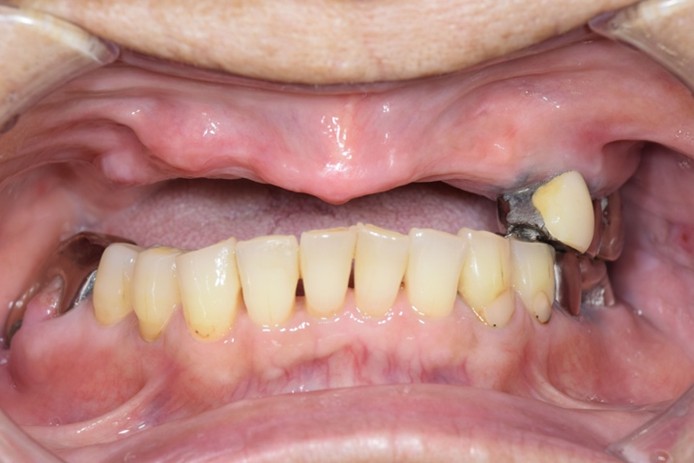

症例1

| 術前 | 術後 |

| ご来院時の主訴 | 入れ歯を入れたが落ちてくる。 インプラントの話を聞いたので入れ歯じゃなくてインプラントをしたい。 |

| 年代・性別 | 70代 女性 |

| 治療部位 | 上顎7〜7 |

| 治療費用 | 2,420,000円 |

| 手術回数 | 2回 |

| 治療期間 | 25か月 |

| 手術時間 | 90分×2回 |

| 治療回数 | 28回 |